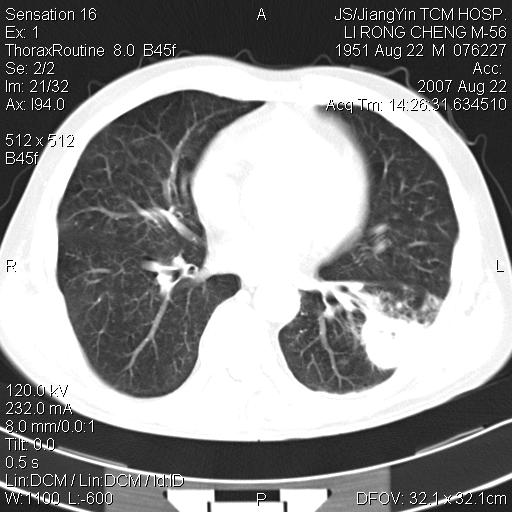

标题: CT9479:M,56Y,DM病史,咳嗽发热5天.肺脓疡.肺癌? [打印本页]

标题: CT9479:M,56Y,DM病史,咳嗽发热5天.肺脓疡.肺癌?

周围有支气管扩张影,伴片块状高密度影,有空洞和胸膜增厚,但是肋骨未见明显破坏,考虑炎性病变可能性大。

左下肺团片状类软组织密度影,形态不规则,边缘欠规整,其内可见液化区及气体影,病灶内侧见引流支气管影,相邻胸膜反应性增厚。病灶周围肺野内见增粗支气管,壁厚,边缘模糊。考虑:支气管扩张并感染;肺脓肿。

支持肺脓肿,左下叶见广泛浸润,并见支扩改变。建议治疗后复查。

考虑左下肺感染,脓肿形成,左下肺支气管扩张,左侧胸膜增厚。其他待排,治疗复查